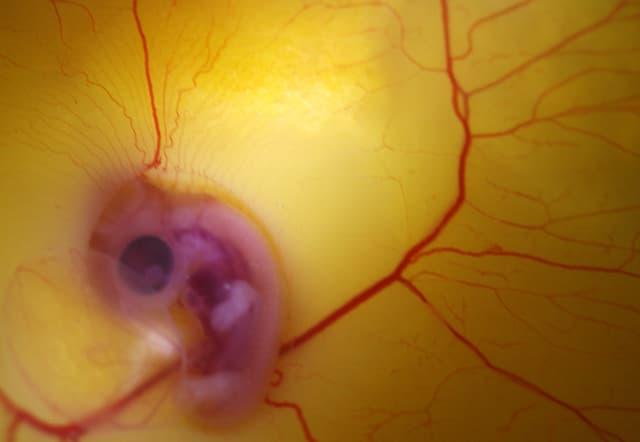

Científicos de la Universidad de Chile decidieron ahondar sobre el misterio mediante la manipulación genética. Los investigadores descubrieron que desactivando el gen IHH de un pollo, la actividad de otro gen, el PTHrP, cobró una inesperada intensidad.

Este nuevo vigor genético animó a los peronés de los pollos a seguir creciendo, hasta unirse a los tobillos, como en sus antepasados los dinosaurios.